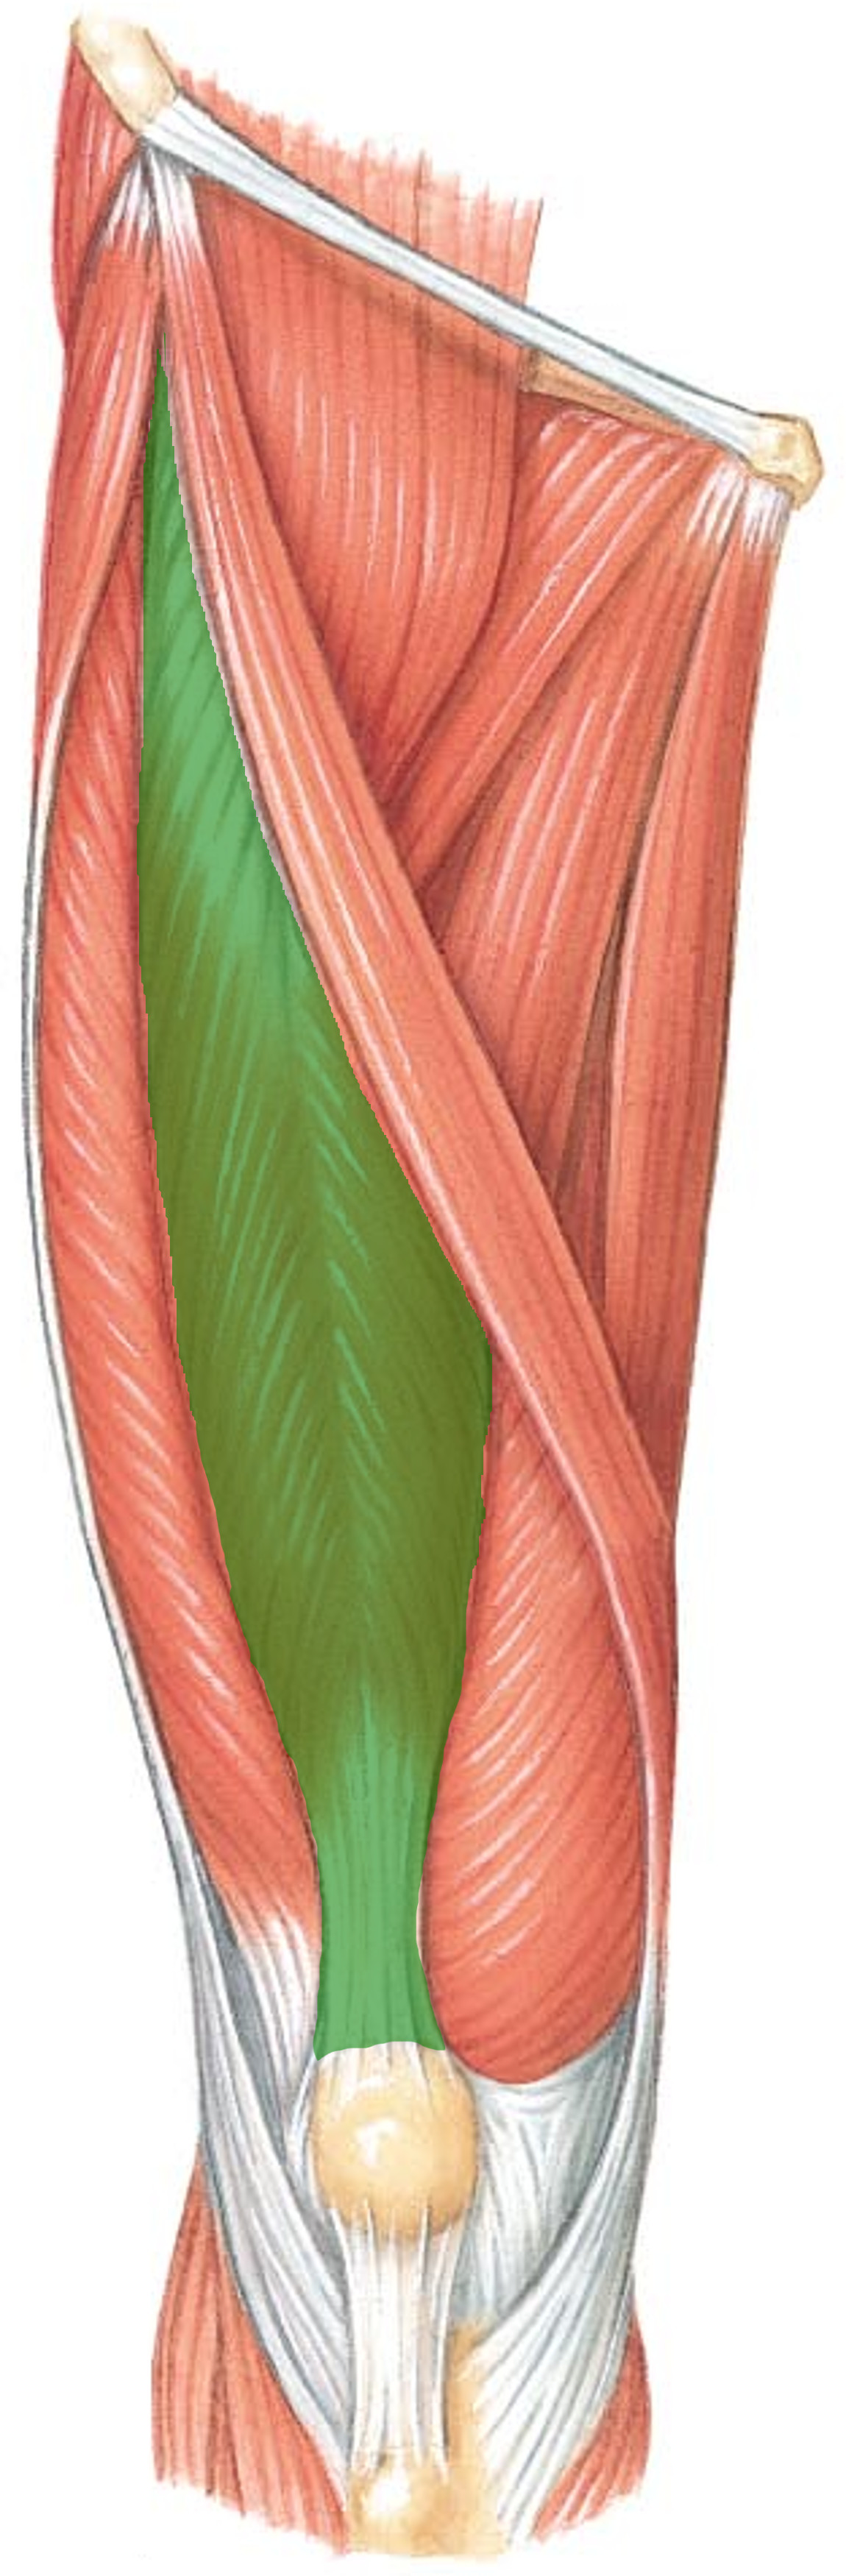

What is the innervation of this muscle?

Muscle - Rectus femoris

Femoral nerve L2-L4